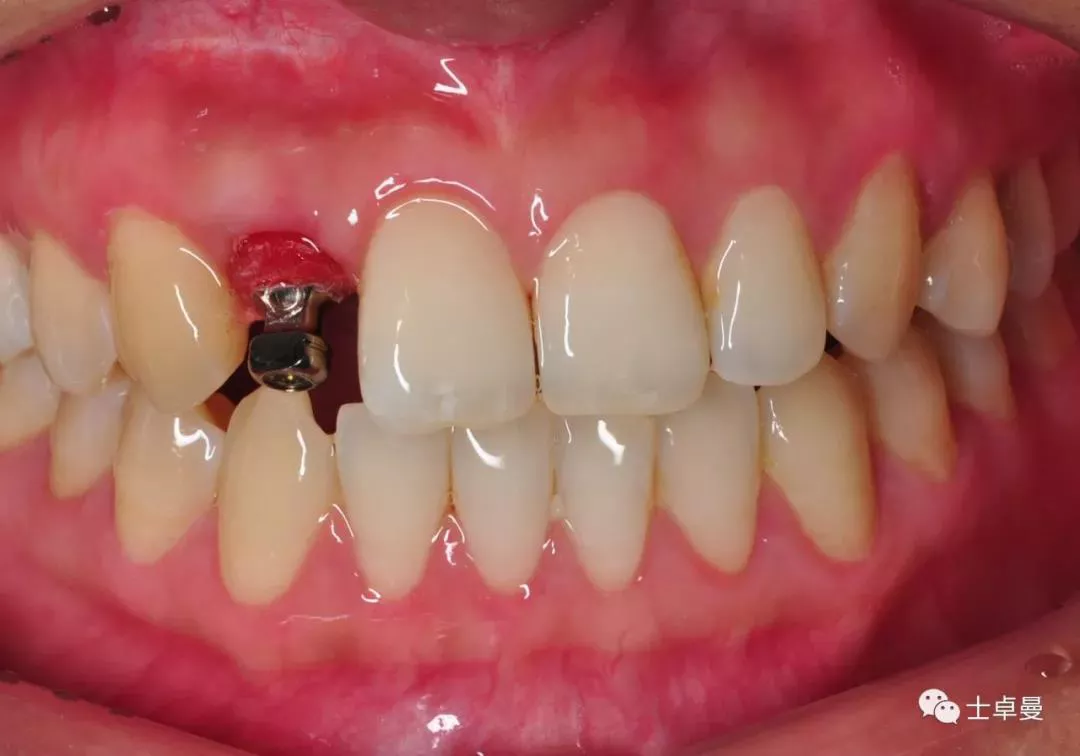

·       临时义齿戴入正中,前伸侧方均无咬合接触;

临时义齿口内就位

·        根尖片显示临时基台就位良好,无骨阻挡;

·        CBCT显示种植体三维位置良好;